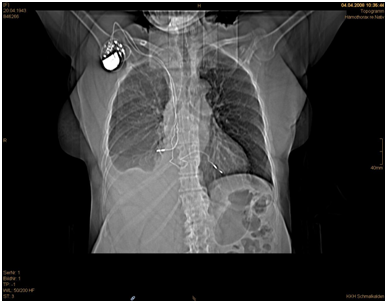

Laboratory examination showed a low haemoglobin level while the other values were in normal rage. Four hours after admission the patient developed more chest pain, respiratory fatigue and became hypotensive. Emergency surgical exploration was decided and performed with median sternotomy. After sternotomy and heart exploration 300 ml bloody pericardial effusion could be extracted. A perforation was found in the middle of the right atrium from the lateral side, with the dislocated lead perforating the pericardium and causing a right lung penetration (Figures 35). The lead was pulled out of the right atrium about 10 cm and cut off. After invagination of the cut off atrial lead in the right atrium the perforated atrium was sewn using a purse-string suture (Prolene 5x0 BB). After opening and exploration of the right pleura 300 ml fixed haematoma and 700 ml bloody pleural effusion were extracted. Subtle inspection of the right lung and sewing of the injury was performed. Chest closure was then performed after placement of two drainage tubes, one retro - cardiac and one right pleural (Figure 6). The patient had a normal recovery without any complications. The patient was discharged after eight days and was planned for a later atrial lead implantation in the future.

Figure 6 Plain chest X-ray after the operation.